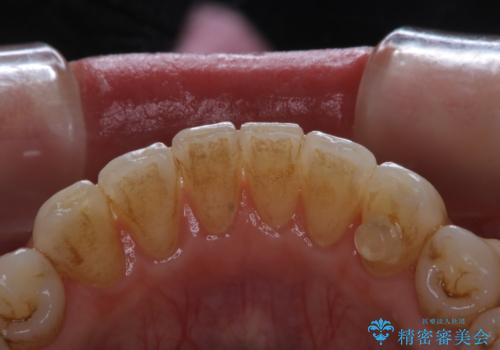

30代男性 PMTCで歯石取り

担当医 歯科衛生士